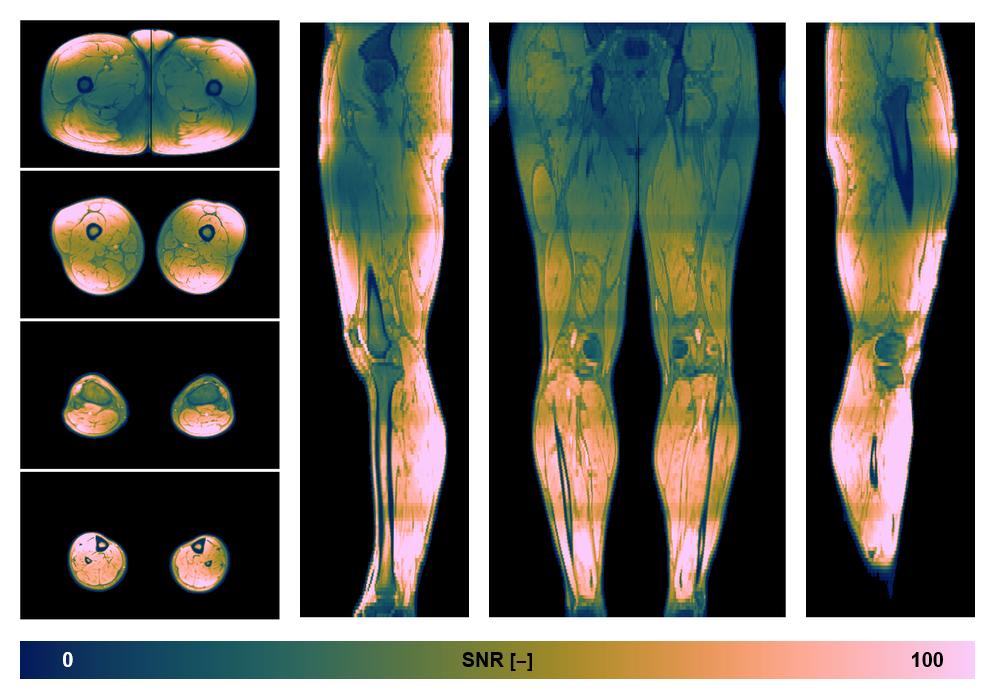

• SNR distribution

The SNR distribution of the dixon data.